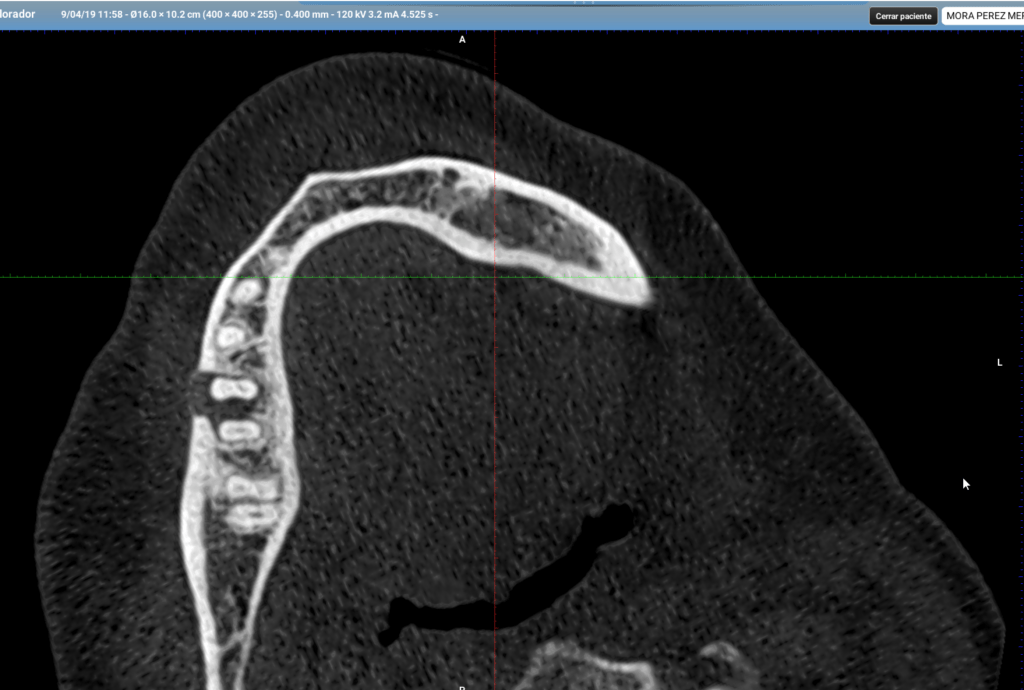

Vertical root fracture